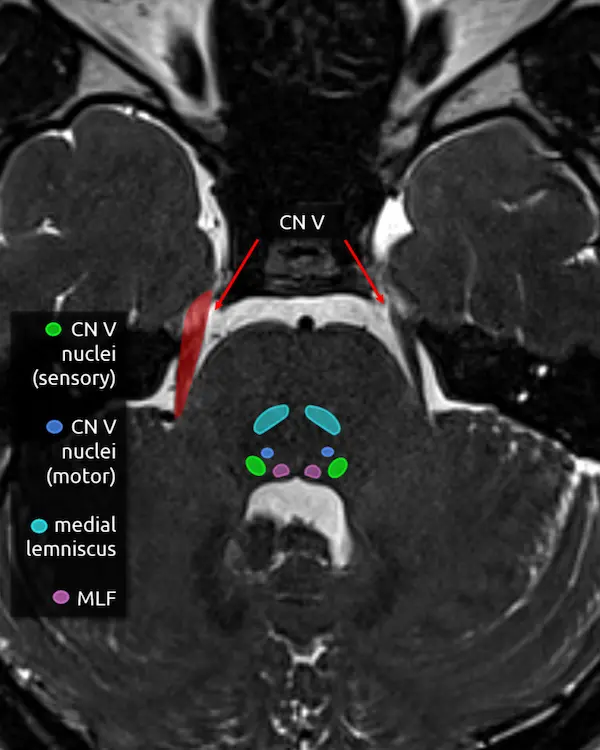

5. Trigeminal nerve (CN V)

The trigeminal nerve is the largest cranial nerve. It exits the side of the pons approximately one slice above the internal auditory canals, then curves forward to traverse the CSF space in front of the pons called the prepontine cistern. It primarily provides sensory innervation to the face, mouth, anterior two thirds of the tongue, nasal sinuses, and dura mater. It has a smaller contribution to motor function of the muscles of mastication.

The trigeminal nerve is large enough to be at least partially visible on routine brain MRIs, though it is sometimes cut off or volume averaged along its course. Notice the image below looks slightly different. This is a heavily T2-weighted sequence with thin slices that is designed to maximize the contrast between CSF and CSF-surrounded structures, usually cranial nerves, blood vessels, or extra-axial lesions. These heavily T2-weighted sequences are useful for ruling out the most common identifiable cause of trigeminal neuralgia: compression by a blood vessel (i.e. neurovascular compression). The region of a cranial nerve most susceptible to symptomatic compression is called the transition zone (aka Obersteiner-Reidlich zone), which is a few millimeters-long gradient of transition from oligodendrocyte myelination (central) to Schwann cells (peripheral). These transition zones are close to where the nerve emerges from the brainstem, called the root entry zone. For the trigeminal nerve, it is 3-4 mm away.

The trigeminal nerve has four nuclei, and two are located around this level.

6. Main sensory nucleus of the trigeminal nerve (CN V)

The main sensory nucleus of the trigeminal nerve is located in the posterolateral pons near the margin of the fourth ventricle approximately one slice above the internal auditory canals.

Lesions in this area will cause ipsilateral sensory loss of the face. A small white matter tract that carries pain and temperature sensation to the body, called the spinothalamic tract (see level 5), is in this region and may be damaged at the same time, resulting in an ipsilateral facial sensory deficit and contralateral body sensory deficit.

7. Motor nucleus of the trigeminal nerve (CN V)

The motor nucleus of the trigeminal nerve is small and located anterior and medial to the main sensory nucleus. As mentioned above, it provides motor innervation to the muscles of mastication primarily, but also to some smaller muscles in the ear and face, for example the tensor tympani muscle and tensor veli palatini.

Damage here may be detectable as weakness and deviation of the mandible or atrophy of the ipsilateral muscles of mastication.